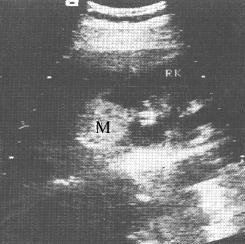

肾错构瘤(B超)

右肾错构瘤。B超示右肾(RK)上极强回声光团(M),与正常肾组织有明显分界,内部光点均匀,后方无声影。